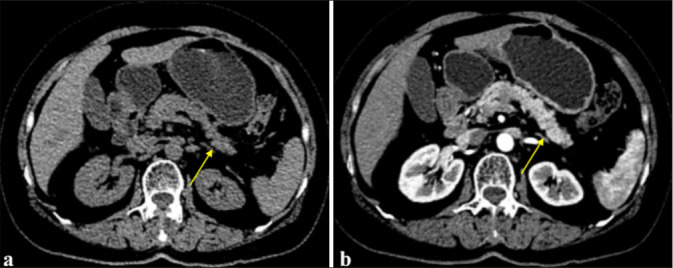

Objective: Histopathology examination is important for diagnosing autoimmune pancreatitis (AIP), which is suspected to be pancreatic cancer based on imaging findings. Although the validity of endoscopic ultrasound-guided fine-needle aspiration (EUS-FNA) in the diagnosis of AIP is still debated globally, this study aimed to evaluate the efficacy of EUS-FNA in the diagnosis of AIP with suspected pancreatic cancer.

Material and methods: From January 2021 to June 2024, 30 AIP patients with radiographically diagnosed pancreatic cancer were enrolled and underwent EUS-FNA. Sex, age, symptoms, CA199, serum immunoglobulin G4 (IgG4), and treatment outcome were included. Tissue sampling conditions, puncture sites, storiform fibrosis, CD38- and IgG4-positive plasma cell counts, and obliterans phlebitis were evaluated.

Results: Thirty patients, 24 males and six females, with an average age of 60.53 ± 11.72 years (32-79 years), were included in the study. Thirty patients had their serum IgG4 and CA199 levels tested. Tissue samples containing ≥10 were obtained from 19 (63.33%) patients. CD38+ plasma cell infiltration and laminar fibrosis were detected in 22 (73.33%) and 10 (33.33%) patients. According to the International Consensus Diagnostic Criteria ( ICDC), 12 patients had histopathological levels of Grade 1, 15 of Grade 2, and three patients could not be classified. The accuracy, sensitivity, and specificity of EUS-FNA in diagnosing AIP with suspected pancreatic cancer on imaging were 96.66% (29/30), 96.42% (27/28), and 100% (2/2), respectively. The area under the curve value of EUS-FNA for patients with AIP who were radiologically suspected of having pancreatic cancer was 0.957.

Conclusion: Approximately 90% of patients with EUS-FNA results are diagnosed with an ICDC level of 2 or higher. Our results suggest that for cases where malignant tumors are suspected after imaging or cannot be ruled out, obtaining pancreatic tissue through EUS-FNA puncture for pathological diagnosis is recommended.